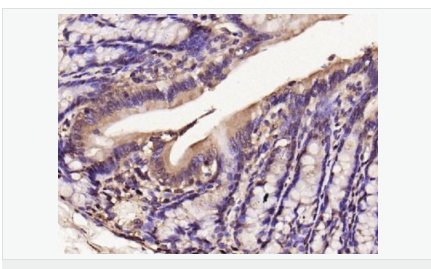

| 產品應用 | WB=1:500-2000 IHC-P=1:100-500 IHC-F=1:100-500 Flow-Cyt=1μg/Test ICC=1:100-500 IF=1:100-500 (石蠟切片需做抗原修復) not yet tested in other applications. optimal dilutions/concentrations should be determined by the end user. |

| 產品介紹 | Nitric oxide (NO) is an inorganic, gaseous free radical that carries a variety of messages between cells. Vasorelaxation, neurotransmission and cytotoxicity can all be potentiated through cellular response to NO. NO production is mediated by members of the nitric oxide synthase (NOS) family. NOS catalyzes the oxidization of L-arginine to produce L-citrulline and NO. Two constitutive isoforms, brain or neuronal NOS (b or nNOS, type I) & endothelial cell NOS (eNOS, type III), and one inducible isoform (iNOS, type II), have been cloned. All NOS isoforms contain calmodulin, nicotinamide adenine dinucleotide phosphate (NADPH), flavin adenine dinucleotide (FAD), and flavin mononucleotide (FMN) binding domains. Nitric oxide synthase is expressed in liver, macrophages, hepatocytes, synoviocytes, stimulated glial cells and smooth muscle cells. Cytokines such as interferon-gamma (IFN), tumor necrosis factor (TNF), interleukin-1 and -2, and lipopolysaccarides (LPS) cause an increase in iNOS mRNA, protein, and activity levels. Protein kinase C-stimulating agents exhibit the same effect on iNOS activity. After cytokine induction, iNOS exhibits a delayed activity response which is then followed by a significant increase in NO production over a long period of time. Human iNOS is regulated by calcium/calmodulin (in contrast with mouse NOS2). Function: Produces nitric oxide (NO) which is a messenger molecule with diverse functions throughout the body. In macrophages, NO mediates tumoricidal and bactericidal actions. Also has nitrosylase activity and mediates cysteine S-nitrosylation of cytoplasmic target proteins such COX2. Subunit: Homodimer. Binds SLC9A3R1. Tissue Specificity: Expressed in the liver, retina, bone cells and airway epithelial cells of the lung. Not expressed in the platelets. Similarity: Belongs to the NOS family. Contains 1 FAD-binding FR-type domain. Contains 1 flavodoxin-like domain. SWISS: P35228 Gene ID: 4843 Database links: Entrez Gene: 4843 Human Entrez Gene: 18126 Mouse Omim: 163730 Human SwissProt: P35228 Human SwissProt: P29477 Mouse Unigene: 709191 Human Unigene: 2893 Mouse Unigene: 10400 Rat Important Note: This product as supplied is intended for research use only, not for use in human, therapeutic or diagnostic applications. 合成與降解(Synthesis and Degradation) 催化生物體內一氧化氮(NO)生成的酶。分神經型一氧化氮合成的酶(nNOS or NOS-1)、誘導型一氧化氮合成的酶(iNOS or NOS-2)、內皮型一氧化氮合成的酶(eNOS or NOS-3)。 |